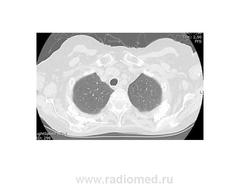

CREST-синдром, или синдром Тибьержа—Вейсенбаха — это тип локализованной системной склеродермии. У больных наряду с кальцинозом кожи, феноменом Рейно, склеродактилией и телеангиэктазиями часто развиваются гиперпигментации, особенно на участках кожи, подверженных солнечному освещению.